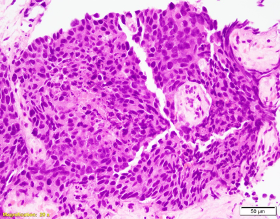

Patient is a 60-year-old male with a “bladder tumor.” Multiple nodules were present in the lung, liver and pelvic lymph nodes. A CT guided biopsy was performed, targeting the hepatic nodules. P40, synaptophysin and chromogranin are negative. MSI studies show loss of MLH1 and PMS2, with retained MSH2 and MSH6.

Picture1 WIN 20201023 14 55 38 ProWIN 20201023 14 56 49 Pro 2020-10-26T17:46:01Z

The patient has metastatic prostate cancer. Immunohistochemical stains are supportive for this diagnosis. NXK3 .1 is helpful in distinguishing poorly differentiated prostatic carcinoma from urothelial. NKX3.1 is a more sensitive and specific than PSAP. Aberrant staining of GATA 3 can be seen in subset set of prostatic carcinomas.  This potential pitfall that may be avoided with more specific and sensitive markers for prostate cancer. MSI loss may be seen in patients with prostatic cancer, however currently there is no increased risk in patients with a family history of prostatic cancer.